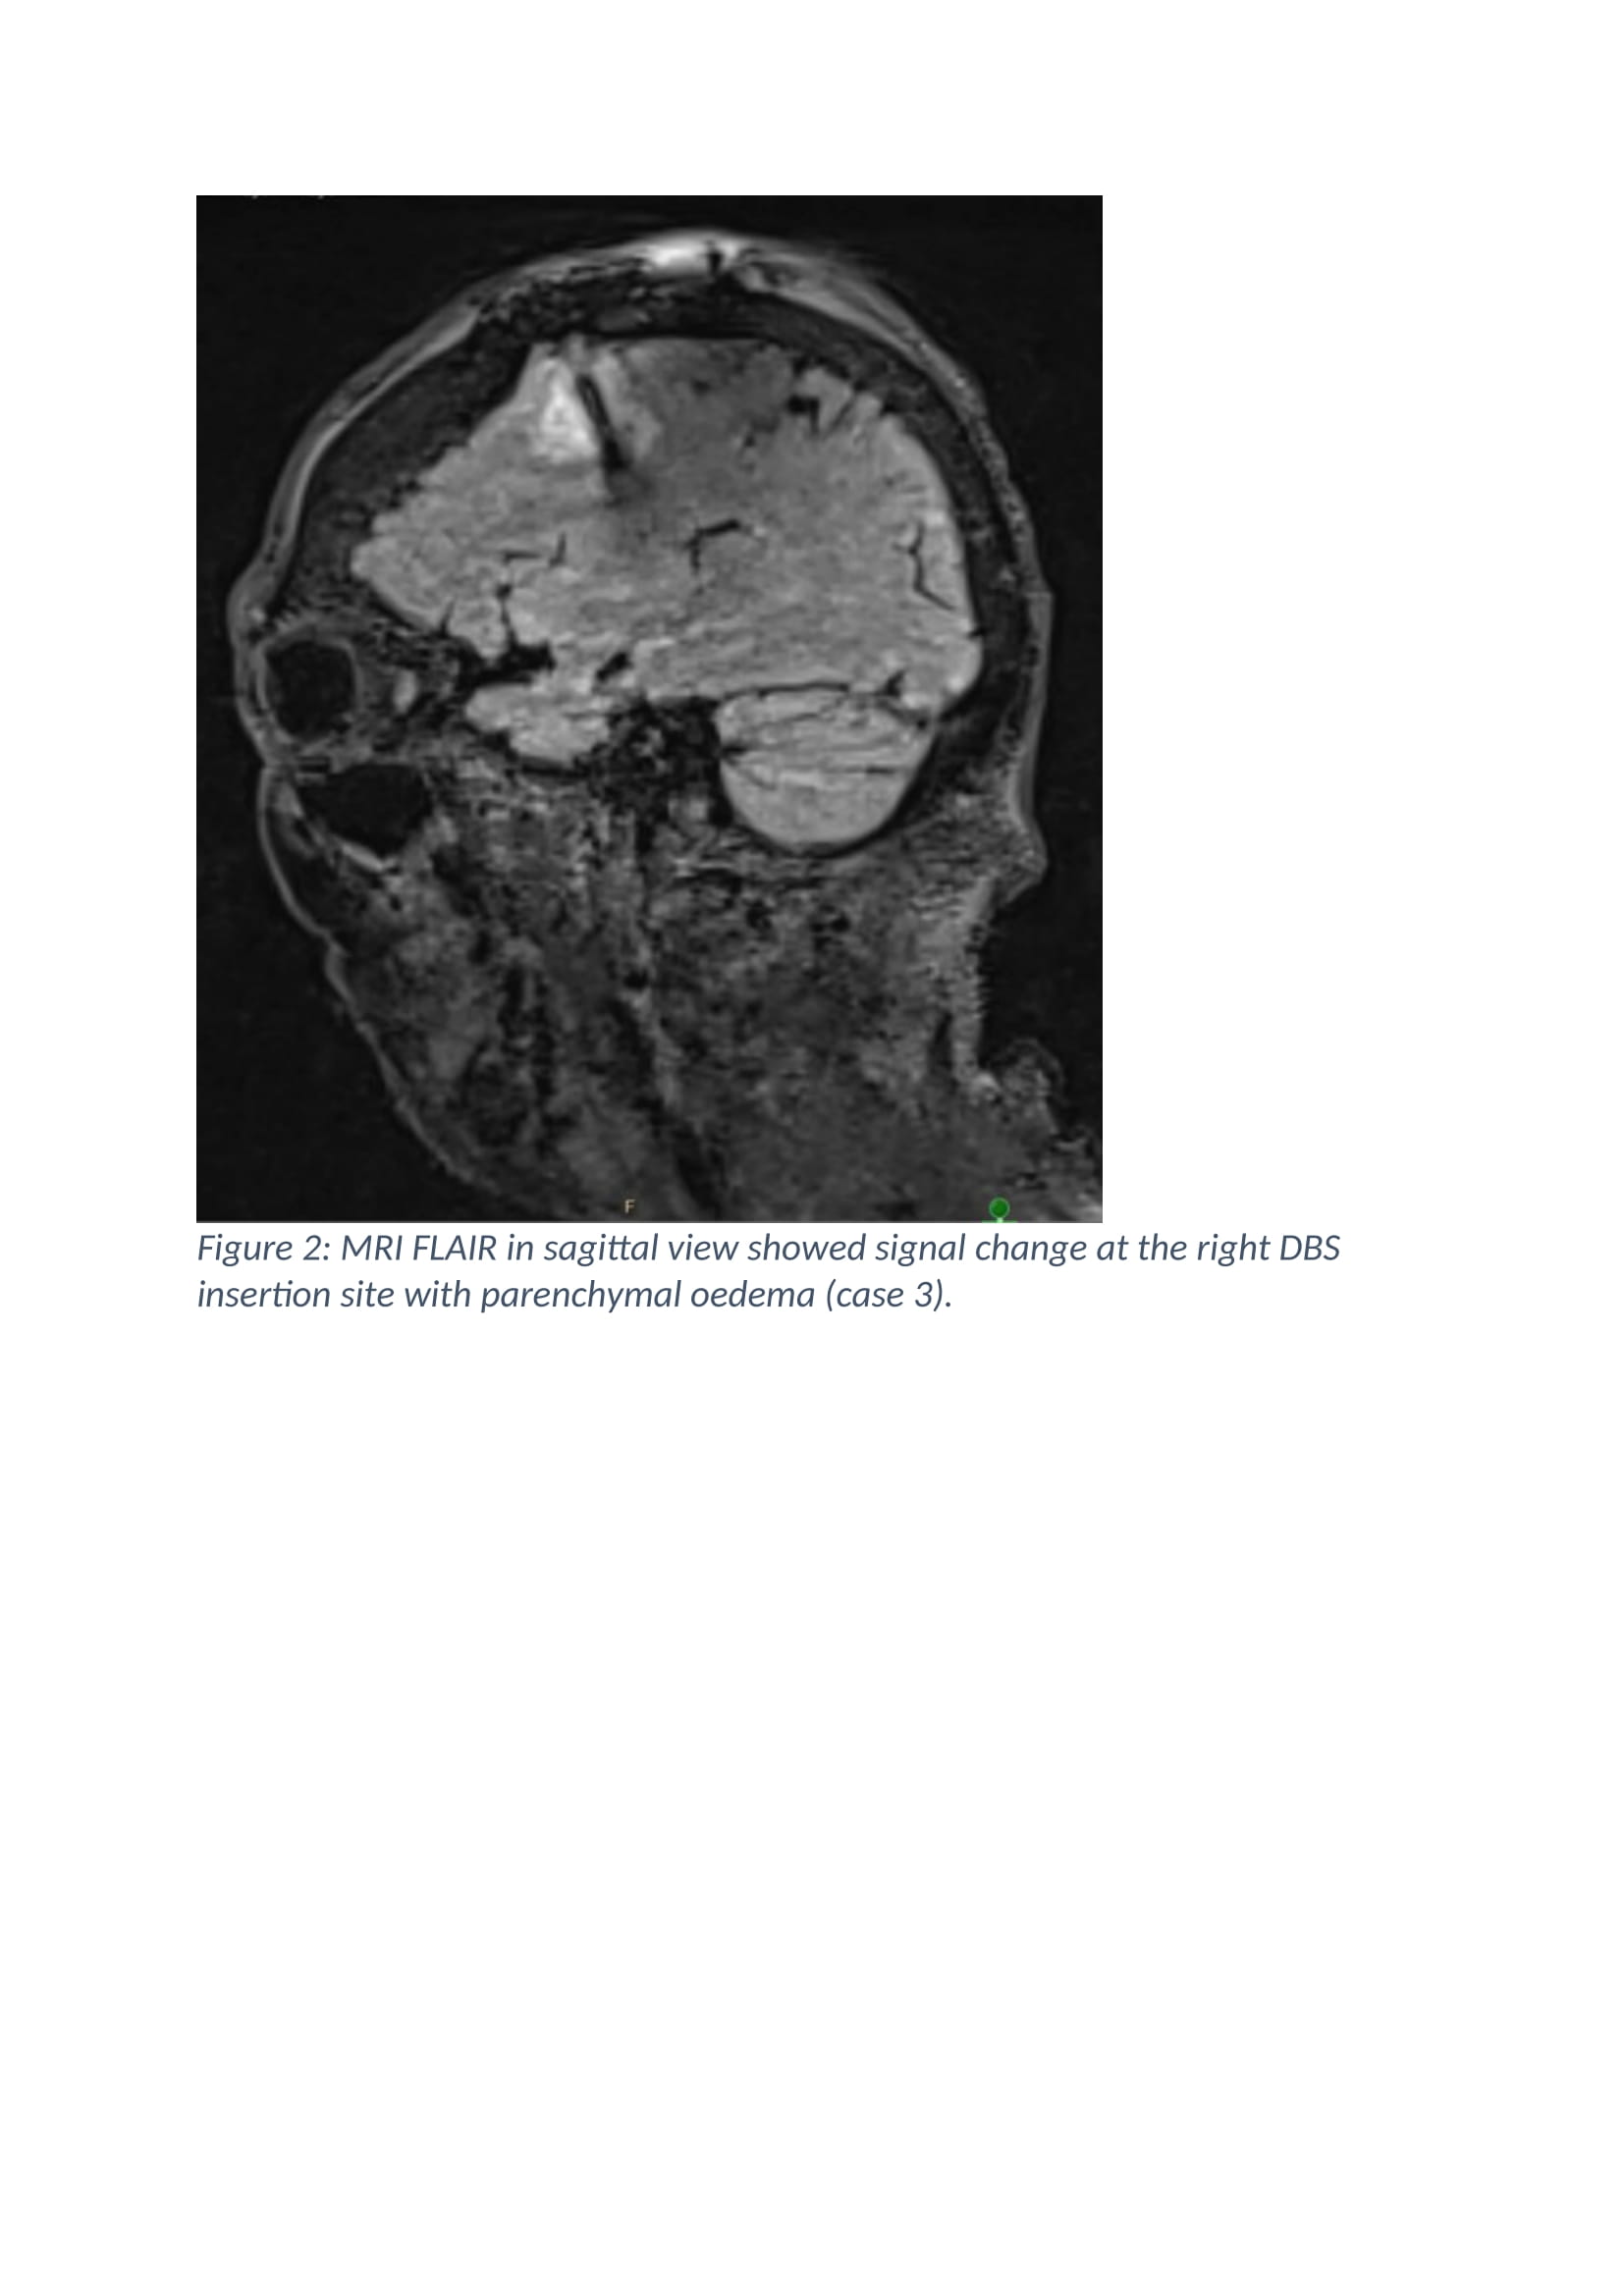

Results: The age at presentation was 62, 63 and 74 years old for case 1, 2 and 3. All the patients were female. The duration of Parkinson’s disease prior to surgery was 14 years, 15 years and 8 years respectively. All patients developed symptoms (confusion, disorientation and seizure) after 24 hours post-operation. There was no fever. Investigations performed did not support infections. EEG performed on all the cases showed asymmetric rhythmic slowing with embedded sharp waves with evolution over anterior head region. The MRI brain imaging detected bilateral asymmetrical peri-lead oedema. Despite treatment with anti-seizure and corticosteroid, patients remain encephalopathic. After clinical consideration, decision was made to remove the DBS implants at day 63, 4 and 9 post-operatives respectively. Brain biopsy results from case 2 revealed features consistent with mild acute encephalitis, however, in case 3; it showed ischaemic, reactive changes with no specific inflammatory process. CSF PCR from case 2 indicated Lactococcus lactis 16s rDNA detected, therefore, she received a 4 weeks course of antibiotics. Investigations for porphyria was performed in view of strong family history however; the result was negative. Follow up EEG showed resolution of epileptiform activity. All patients improved soon after and underwent rehabilitation.

Figure 2